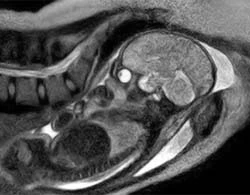

Ảnh scan đầu tiên trên thế giới về giây phút bé chào đời

Lần đầu tiên, các bác sĩ đã tạo ra bức ảnh MRI sống động về đứa trẻ ở khoảnh khắc lọt lòng mẹ. Các bức ảnh này là nguồn thông tin giá trị giúp hiểu sâu về quá trình sinh nở và cho phép cứu sống các em bé trong tương lai.

Em bé chào đời qua ngả âm đạo của mẹ. Ảnh chụp từ hệ thống máy MRI đặc biệt của các bác sĩ Đức.

Để có ca ghi hình này, nhóm nghiên cứu đã phát triển một máy scan "mở" đặc biệt, trong đó ôm lấy căn buồng nơi các bác sĩ và y tá đỡ đẻ cho người mẹ. Bệnh viện cho biết cả mẹ và bé hiện đều trong tình trạng sức khỏe tốt.

Việc tạo ra các hình ảnh MRI về ca sinh nở có thể giúp khắc phục những biến chứng khi sinh, và giúp các bác sĩ hiểu rõ tại sao 15% số bà bầu phải mổ đẻ do đứa bé di chuyển không tốt theo đường âm đạo.